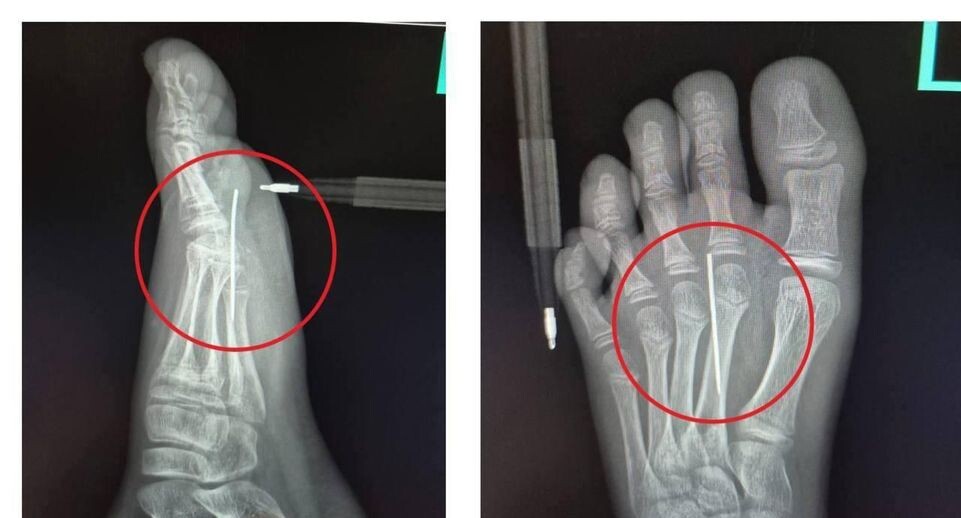

Наступившего на иголку ребенка спасли в медцентре Рошаля

В медицинском центре специалисты сделали рентген и убедились, что в стопе есть инородное тело.